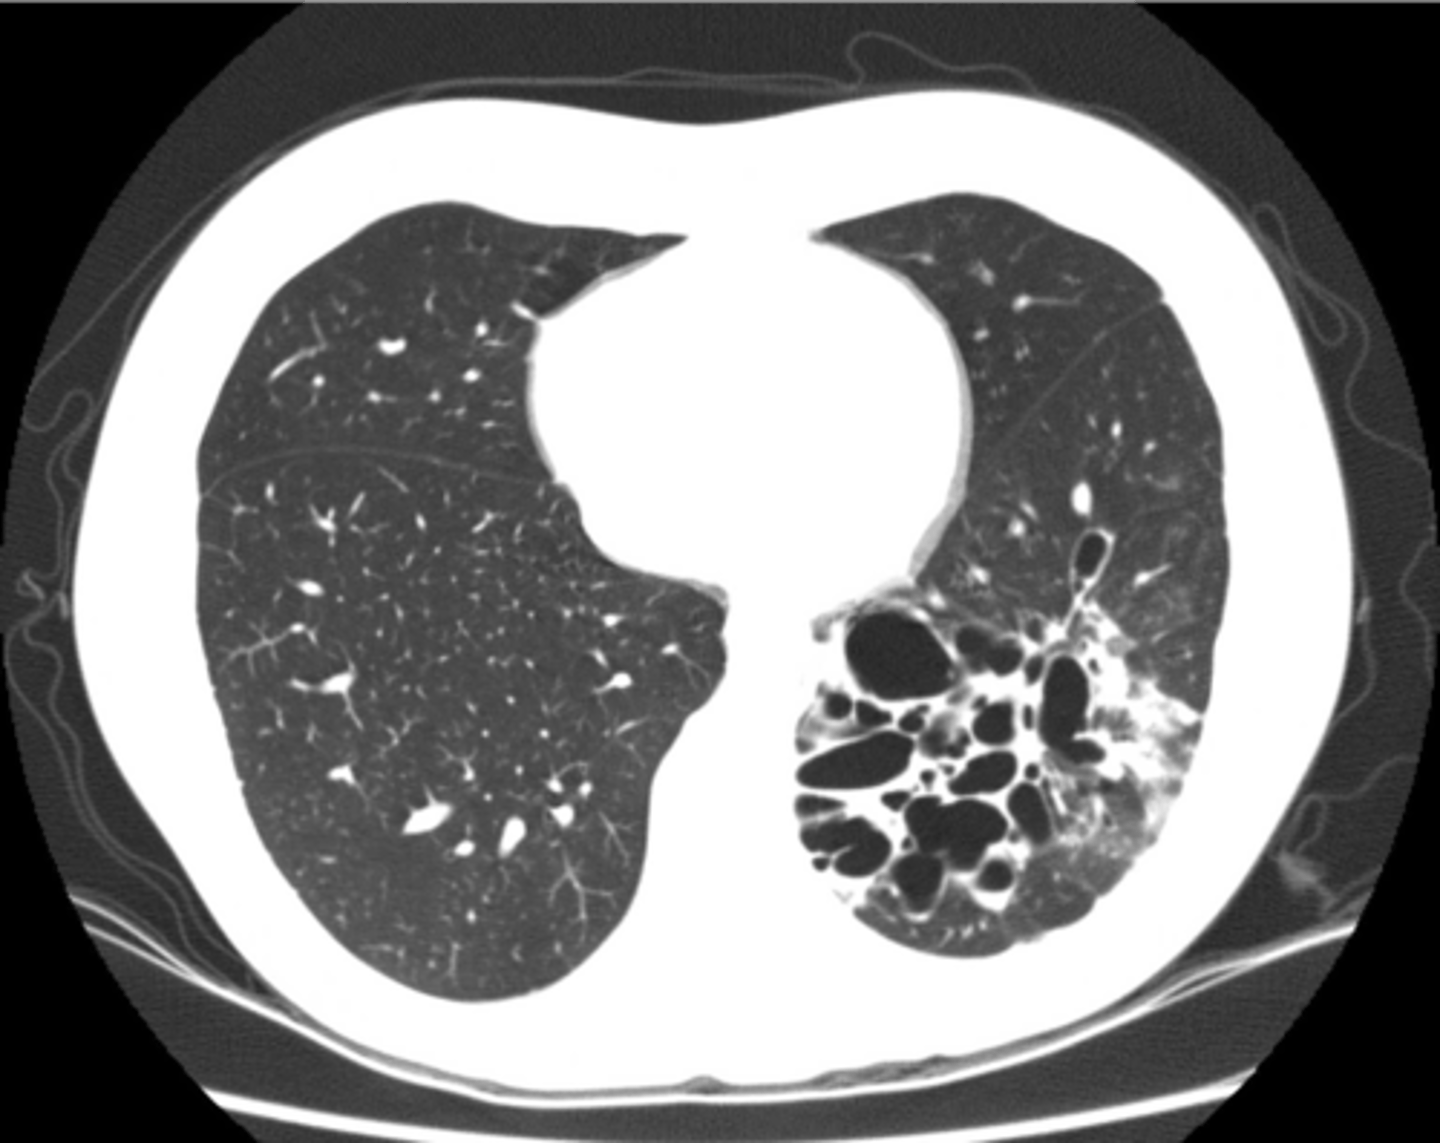

Lung tissues with air space but no alveoli thats less than 1 cm in diameter

Bleb

Lung tissues with air space but no alveoli thats greater than 1 cm in diameter

Bullae

RUL bullae

Flattening of hemidiaphragms

& blunting of costophrenic angles, Increased AP diameter (barrel chest), bullae or large air cavities indicates

hyperinflation

COPD/Emphysema

COPD/Emphysema

Bullae RUL